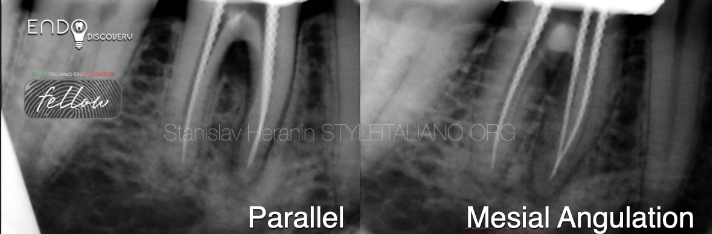

X线片检查

远中根管:MTA封闭